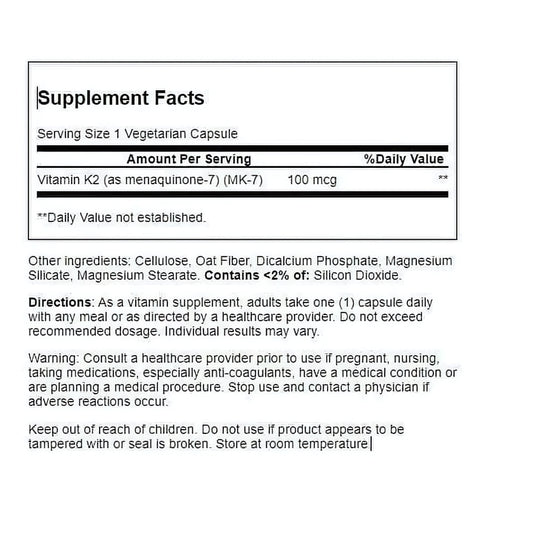

21st Century K2 MK-7 100 mcg 110 Veg Capsules

Regular price Tk 2,450.00 BDTRegular priceUnit price / perTk 2,950.00 BDTSale price Tk 2,450.00 BDTSale -